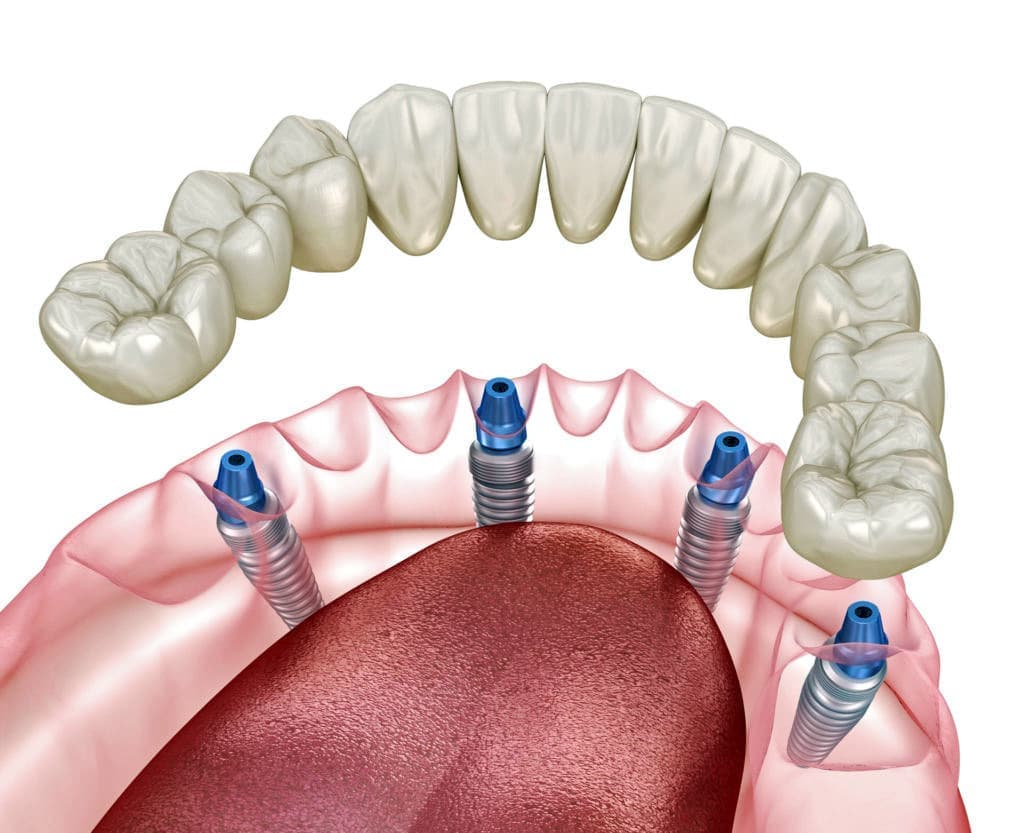

人工骨予備手術

インプラント治療にて難症例といわれる、骨が薄い、不足している、移植が必要などの状況にでくわすことがあります。

そのような方はインプラント治療を受けるために骨の厚みを増やさなくてはなりません。

当院では、これら難症例にも対応しており、様々な術例における人工骨予備手術も可能です。